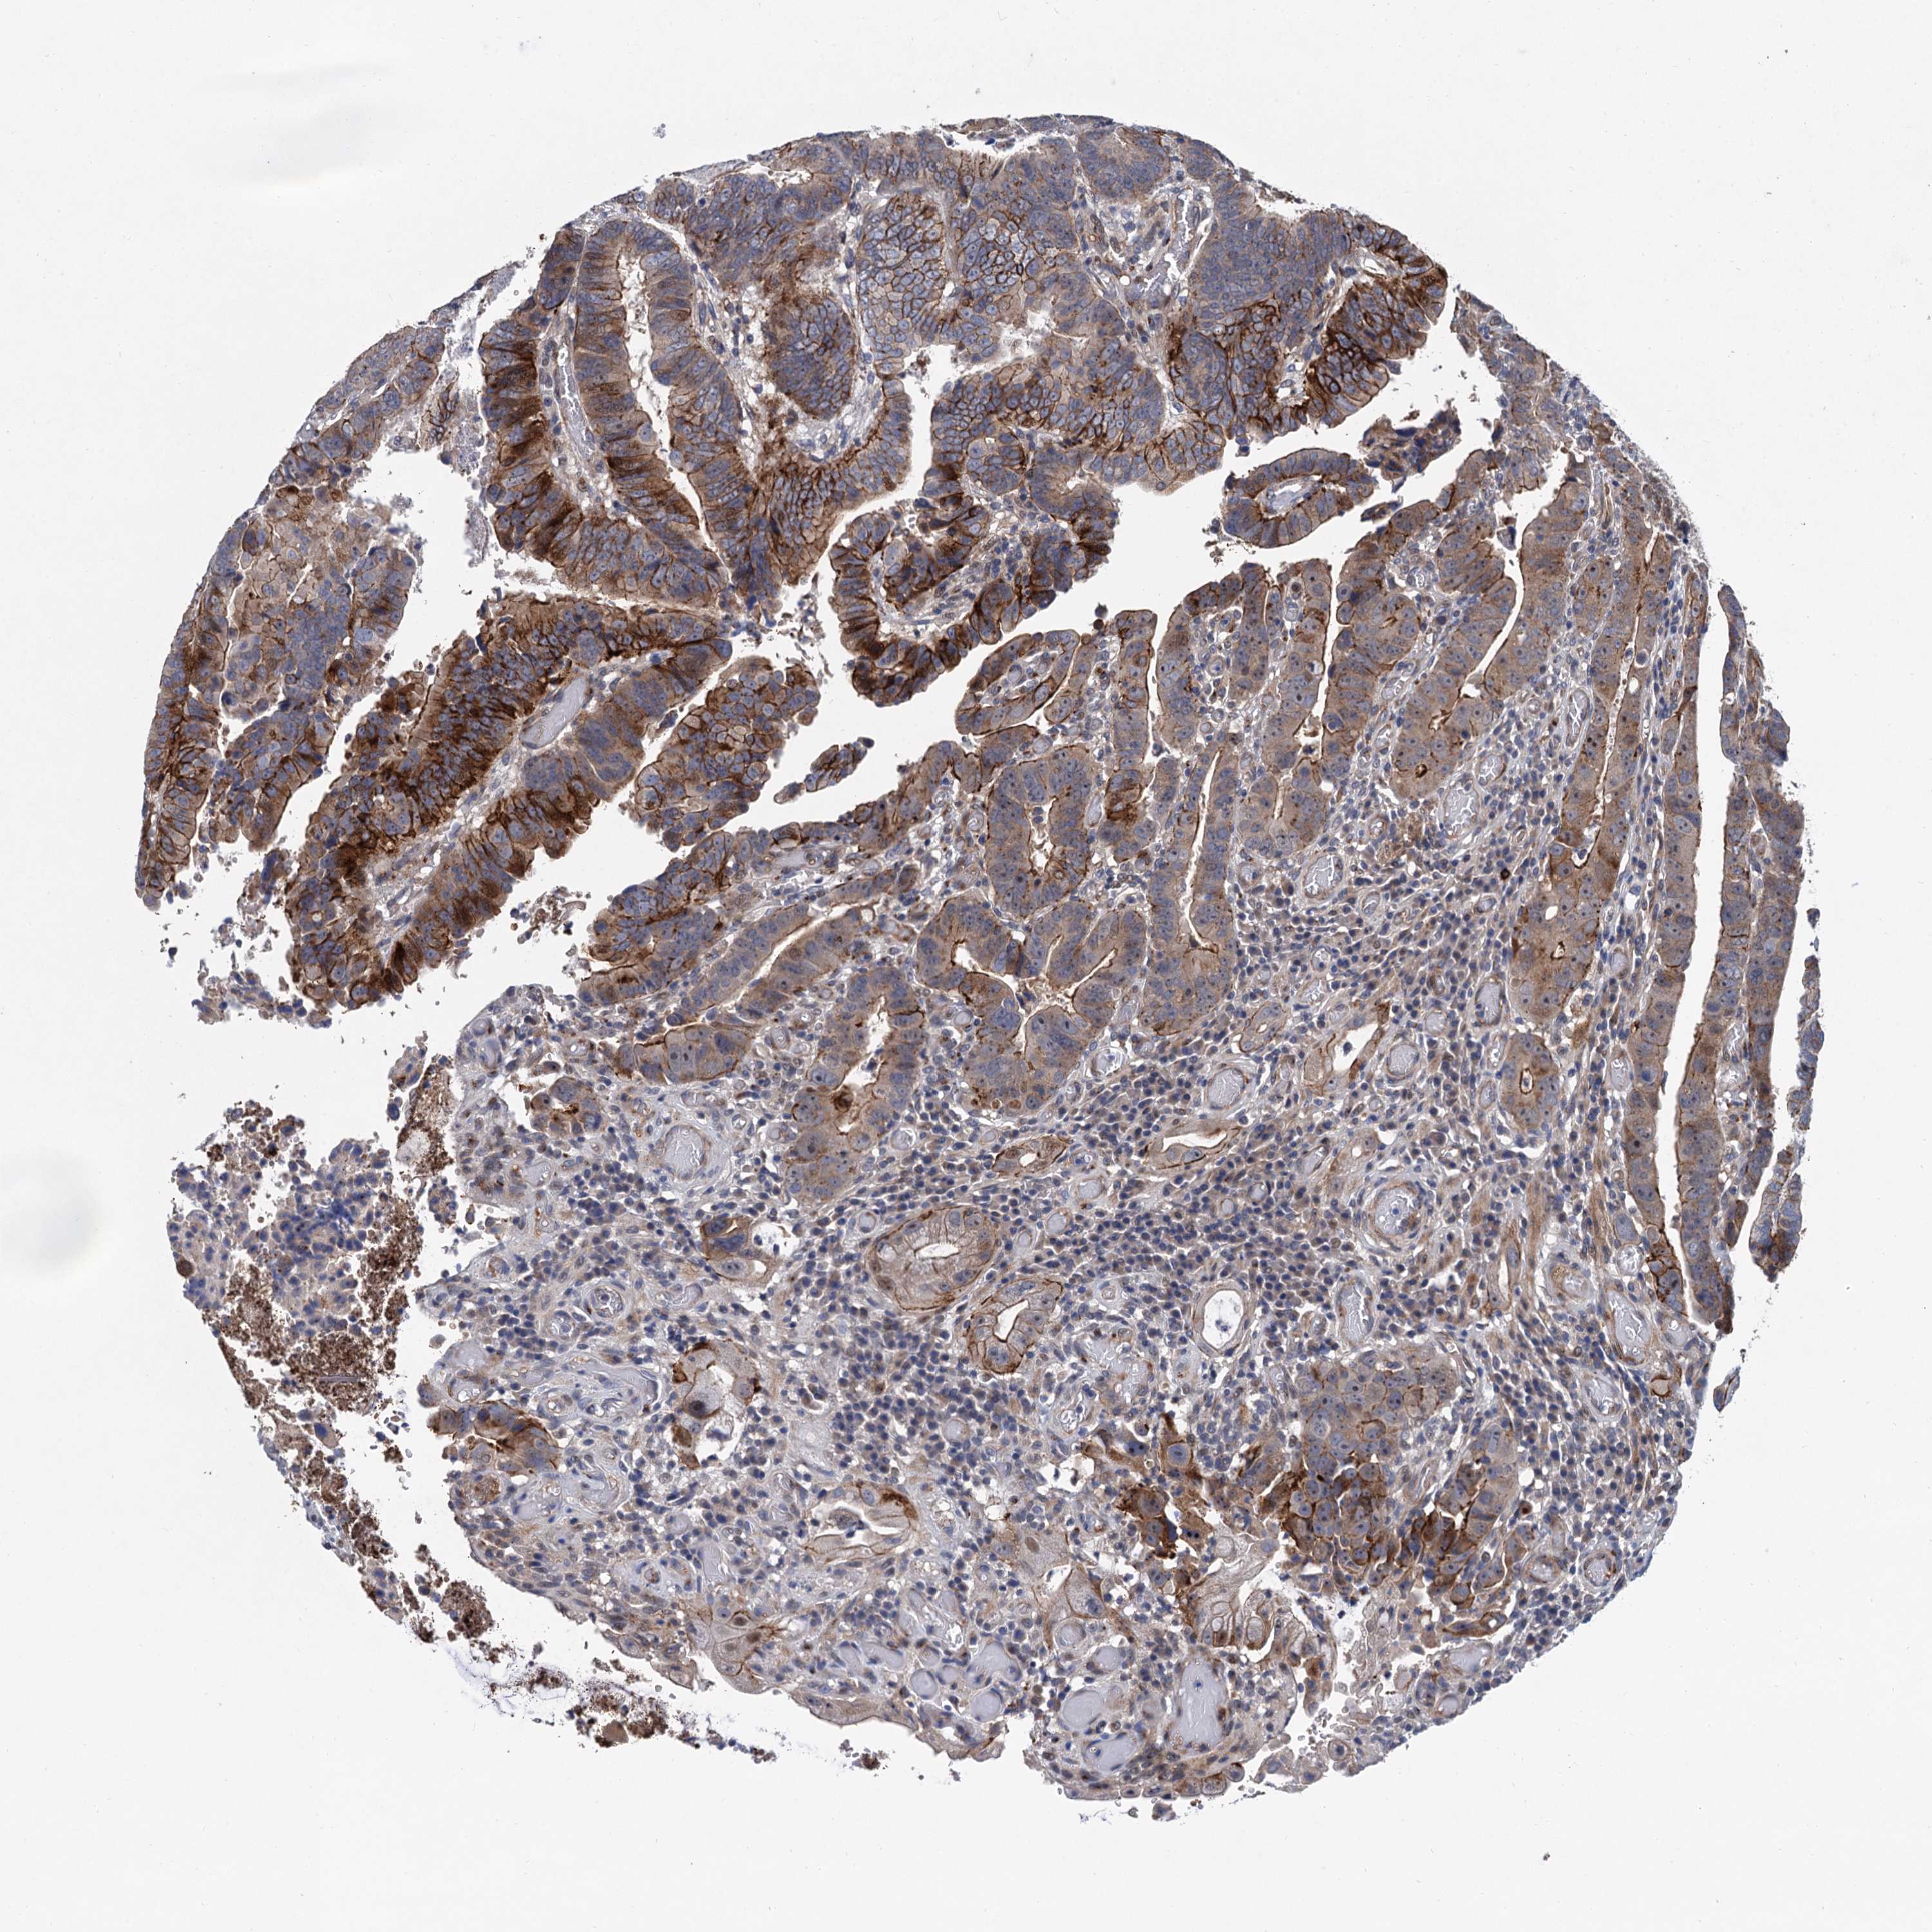

CANCER COLORECTAL CANCER Show tissue menu

Colorectal cancer

Human cancer

Colon adenocarcinoma